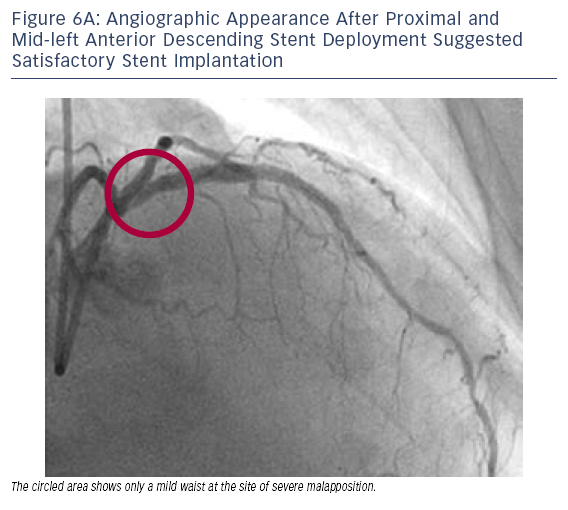

• PCI was performed with placement of a 3.0 x 38 mm stent and a very satisfactory result by angiography was achieved (see Figure 6A).

• OCT was performed after stent implantation; however, reveImage titlealed gImage titleross stent malapposition (see Figure 6B).